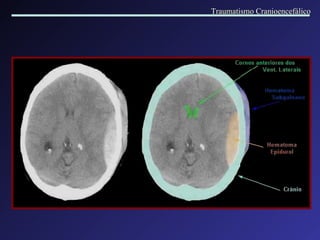

Formado entre o crânio e a dura, a partir do sangramento de vasos meníngeos. Associados a fraturas e outros tipos de lesões. Localização: Temporo-parietal. Quando > 40 ml = 100% mortalidade. Velocidade de instalação; efeito de massa. Intervalo lúcido. Hemorragia Extra axial   Hematoma Epidural Traumatismo Cranioencefálico

Hematoma Epidural  parietal direito : not a -se o aspecto lenticular da lesão e desvio da linha mediana. Traumatismo Cranioencefálico

Hemorragia Extra axial Hematoma Subdural Agudo   Formados entre a duramater e a aracnóide, por lesão de veias córtico-meníngeas. Este espaço é facilmente dilatável, possibilitando grandes acúmulos de sangue. Causas: quedas ou agressão. Lesões associadas. Intervalo lúcido. Coleção em crescente, com efeito de massa variável. A cirurgia normalmente está indicada. Traumatismo Cranioencefálico